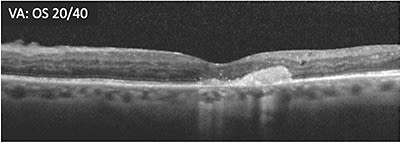

A 65-year-old male patient with proliferative diabetic retinopathy (PDR) who had undergone vitrectomy for nonclearing vitreous hemorrhage presented 2 months later. OCT showed substantial cystoid macular edema and hyperreflective foci (A) and he had poor vision (20/200 OS). The patient was started on treatment. Three months later, the retina was less swollen, but some macular edema remained, vision was 20/200, and cystic changes persisted (B). Treatment was switched within the same class in an effort to address the remaining macular edema. At 4 weeks following the initial treatment with the second therapy, vision remained poor (20/200 OS) and cystic spaces remained (C). Over the course of the next 8 months, the patient received 8 more treatments with the second therapy. Visual acuity was 20/100 -2 while the appearance of the cystic edema on OCT worsened (D).